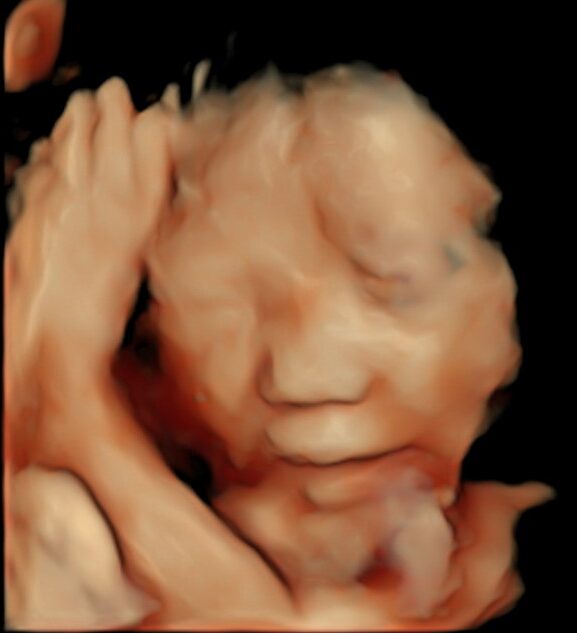

条件が良ければ、こんな感じで赤ちゃんをみることができます(写真は、お母さんにホームページに載せることを許可していただいています)。

赤ちゃんの協力も必要なので、残念ながらいつもこのようにみえるわけではありまんが、

お腹の中で元気に育っている姿をみると、幸せのおすそ分けをしてもらっているような気分になります。

一番はじめのエコー画像は妊娠9週のものですが、この時期ですでに頭も手も足もしっかりできています。